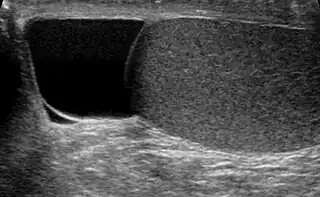

Testículo (en gris) y espermatocele (en negro) | ||

Hallado indoloramente, la masa quística en la cabeza del epidídimo, con diafanoscopia se ve claramente diferenciado del testículo, y es generalmente suficiente. Si existe incerteza, la ultrasonografía de escroto puede confirmar si es espermatocele.